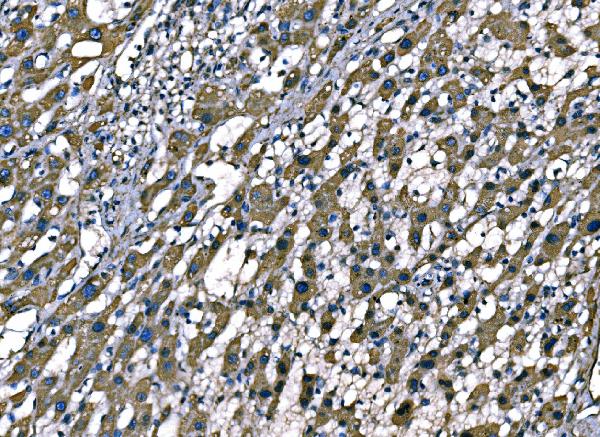

(Figure 3. IHC analysis of SOD2 using anti-SOD2 antibody (AAA126866).SOD2 was detected in a paraffin-embedded section of human liver cancer tissue. Heat mediated antigen retrieval was performed in EDTA buffer (pH 8.0, epitope retrieval solution). The tissue section was blocked with 10% goat serum. The tissue section was then incubated with 2 ug/ml mouse anti-SOD2 Antibody (AAA126866) overnight at 4 degree C. Peroxidase Conjugated Goat Anti-mouse IgG was used as secondary antibody and incubated for 30 minutes at 37 degree C. The tissue section was developed using HRP Conjugated Mouse IgG Super Vision Assay Kit with DAB as the chromogen.)